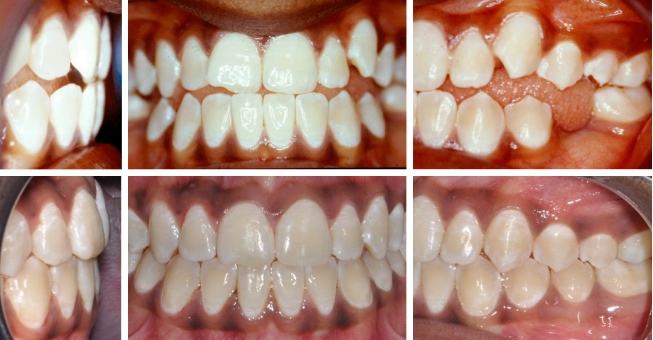

Fall 4: Kopfbiss / Unterkiefervorlage mit seitlich offenem Biss

Therapie: Festsitzende Spange